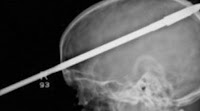

Un arpón le atraviesa la cabeza, y se salva.

Nasser López, un joven de 16 años, se salvó de milagro después de que un arpón disparado accidentalmente por un amigo le atravesará el cerebro, literalmente, de lado a lado.

Nasser estaba nadando en un lago situado en las inmediaciones de su casa, en Miami, mientras un amigo suyo, se encontraba en la orilla manipulando un arpón. En ese momento, el proyectil del arma se le disparó, con la mala suerte de que impactó directamente en la cabeza del joven.

Venciendo el pánico que le produjo la escena, y tras pensar en una primera instancia que había matado a su amigo, el muchacho consiguió avisar a las emergencias para que trasladaran a su amigo al Hospital Jackson Memorial de Miami.

Según informa The Miami Herald, los médicos que atendieron a Nasser aseguran que han salvado su vida milagrosamente, aunque tienen que evaluar ahora qué daños ha producido el arma. Su primera obsesión era estabilizar el proyectil para evitar que se moviera y rasgara más zonas del cerebro.

El chico se recupera satisfactoriamente de las heridas. "Es un verdadero milagro que el arpón no haya tocado los principales vasos sanguíneos del cerebro", reconoció a los medios de comunicación el neurocirujano del Jackson Memorial Ross Bullock.